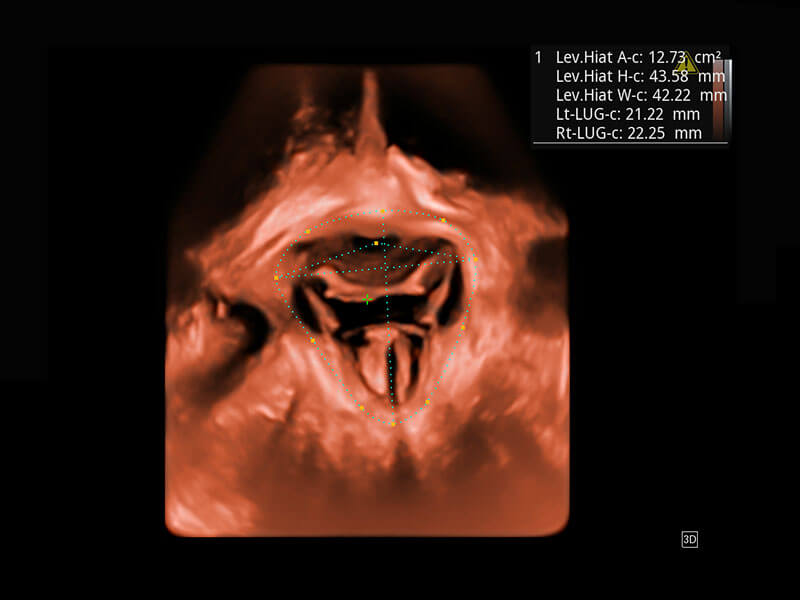

P60為盆底超聲檢查提供應(yīng)用方案,多種腔內(nèi)及腹部容積探頭提供從二維、三維到四維的優(yōu)異圖像品質(zhì),實時快速三維容積數(shù)據(jù)獲取,專業(yè)的測量工具包等人性化設(shè)計,為超聲醫(yī)生診斷提供有力保障。

Lev.Hiat A-r: 16.33 cm2

Lev.Hiat H-r: 53.70 mm

Lev.Hiat W-r: 43.96 mm

Lt-LUG-r: 24.16 mm

Rt-LUG-r: 19.94 mm

能夠簡化盆底檢查的操作流程,可在二維模式及三維成像模式下實現(xiàn)一鍵自動提取出標準切面、自動識別當前切面、自動測量,提升盆底檢查的高效性,同時也能讓青年醫(yī)生快捷的獲得準確的檢查結(jié)果。